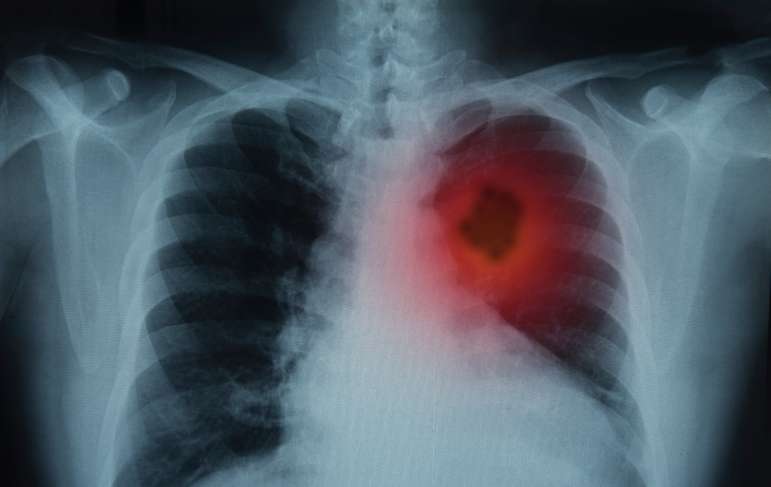

Lung cancer is also caused by asbestos. Asbestos is a group of six fibrous silicate minerals that was used for its many industrial applications. It was used as insulation because it is fireproof and resists heat very well. It can also be sewn into fabrics, allowing people to wear clothing that protected them from heat and fire, but endangered their lives when wearing it. Movement and agitation of asbestos releases the fibers into the air, which are then inhaled, becoming lodged in lungs and other tissue. The fibers are indestructible, so the body cannot break them down or remove them and over time, the asbestos causes DNA changes in cells, which then leads to cancer.

Asbestos also causes mesothelioma, the cancer of the mesothelium. There are four different types of mesothelioma including pleural (lungs), peritoneal (abdominal), pericardial (heart), and testicular (testicles). Mesothelioma is a rare cancer, but it still needs to be prevented. There are only around 3,000 new cases of mesothelioma diagnosed every year, but this does not mean that asbestos can be taken lightly. If you have the option to avoid asbestos, it is in your best interest to prevent exposure, which can help prevent mesothelioma and lung cancer.